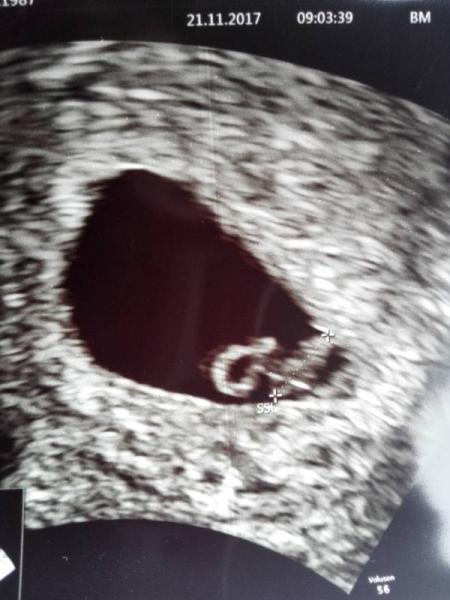

Ich wollt mal kurz âHalloâ sagen. Meine Mama und mein Papa waren sehr ergriffen, als sie mich mit blubbernden sahen.

Ich bin noch etwas klein fĂŒr 6+6. 6mm sprach fĂŒr 6+3, aber die Ărztin meinte, dass sich das noch Ă€ndern kann, weil ich noch etwas klein zum Vermessen war. Sie schaut in 2 Wochen noch einmal nach mir. In der Zeit werde ich mich anstrengen und noch etwas wachsen.

P.S.: Wenn ihr wollt, dĂŒrft ihr mein erstes Foto bewundern.